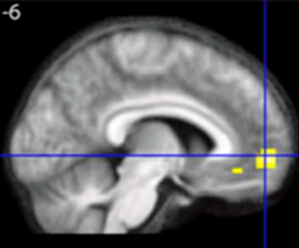

关于美学最新的神经学研究显示,视觉、听觉和道德上的美感体验都与“情绪化大脑”的同一个区域有关:内侧眶额叶皮层(medial orbitofrontal cortex,mOFC)的A1区。

通过大脑扫描,研究者发现体验数学之美的区域与之前发现的与视觉、听觉和道德美感相关的区域并无二致,即都是内侧眶额叶皮层的A1区。不仅如此,这种感觉越强烈,这个区域的大脑就越活跃。

有意思的是,理解公式与否与是否能体验其美感并无严格关联。即便是非数学专业的受试者也会感觉一些公式更美,虽然他们不能理解其含义。内侧眶额叶皮层A1区的活动与对美的评判相关,而与理解无关。

需要注意的是,这些发现并不意味着内侧眶额叶皮层是唯一同数学之美相关的脑区。还有一些在看到美丽图案或者听音乐片段时没有激活的脑区在看到数学问题时活跃了起来。事实上,研究表明的是在经历看似不同的美感刺激时,内侧眶额叶皮层A1区的活动似乎是它们之中的共通之处。

此外,这一结果也同样不意味着这一区域只用于体验美。内侧眶额叶皮层A1区还有很多功能,包括情感、学习、快乐以及获得奖赏。

最后要明确的是,研究结果也不意味着内侧眶额叶皮层A1区的神经元产生了对数学美的体验。结果仅仅表明大脑活动与看到数学公式时体验美有相关性。